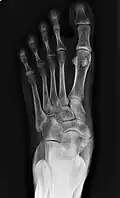

Radiological images

-

From left to right: Type 1, 2 and 3 -